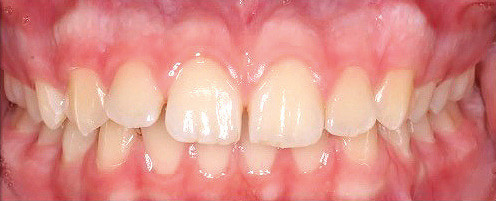

Klinisches Fallbeispiel 2 (Abb. 2a–y)

Distalbiss und tiefer Biss bei einem zwölfjährigen Mädchen. Die Behandlung erfolgte mit Invisalign und Precision Wings. Insgesamt waren zwei Schienensätze notwendig. Die Gesamtbehandlung dauerte 18 Monate.Bei der Planung des ClinCheck wurde der tiefe Biss vorwiegend über eine Intrusion der Unterkieferfront behoben, um die Lachlinie der Patientin nicht negativ zu beeinflussen. Die Oberkieferfront wurde nur retrudiert, jedoch vertikal nicht intrudiert. Während der Phase des Mandibular Advancement wurde die Wirkung der Precision Wings durch den Einsatz von Klasse II-Gummizügen unterstützt. Schlussendlich wurde auch der hängenden Okklusionsebene durch eine einseitige Intrusion der Molaren im ersten Quadranten Rechnung getragen.